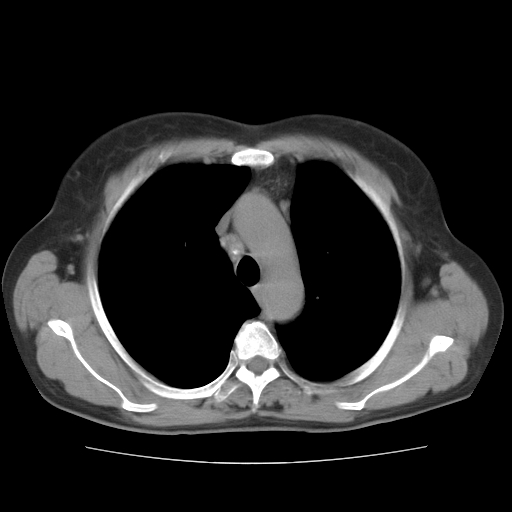

标题: CT10838:女性,56岁,是上腔静脉钙化还是淋巴结钙化? [打印本页]

标题: CT10838:女性,56岁,是上腔静脉钙化还是淋巴结钙化?

女性,56岁临床诊断为胃贲门ca,术前检查发现,此钙化灶,对此科内稍有争论!请各位老师看看!是上腔的还是淋巴结的?有意义吗?

胸锁关节层面的是淋巴结钙化,气管前腔静脉后的钙化灶占了4个层面,不知层厚是多少?看样子应该是7--10毫米之间,那么这病灶最小纵径得有28毫米!应该提示点什么了,没传肺窗,估计肺内没有病变?

左锁骨下静脉和头臂静脉会合后形成是上腔静脉,此钙化位于两血管回合的腔静脉后方、气管右前方,这个位置没有其他结构,应该是淋巴结钙化。一般多为淋巴结核后钙化,没有临床意义。